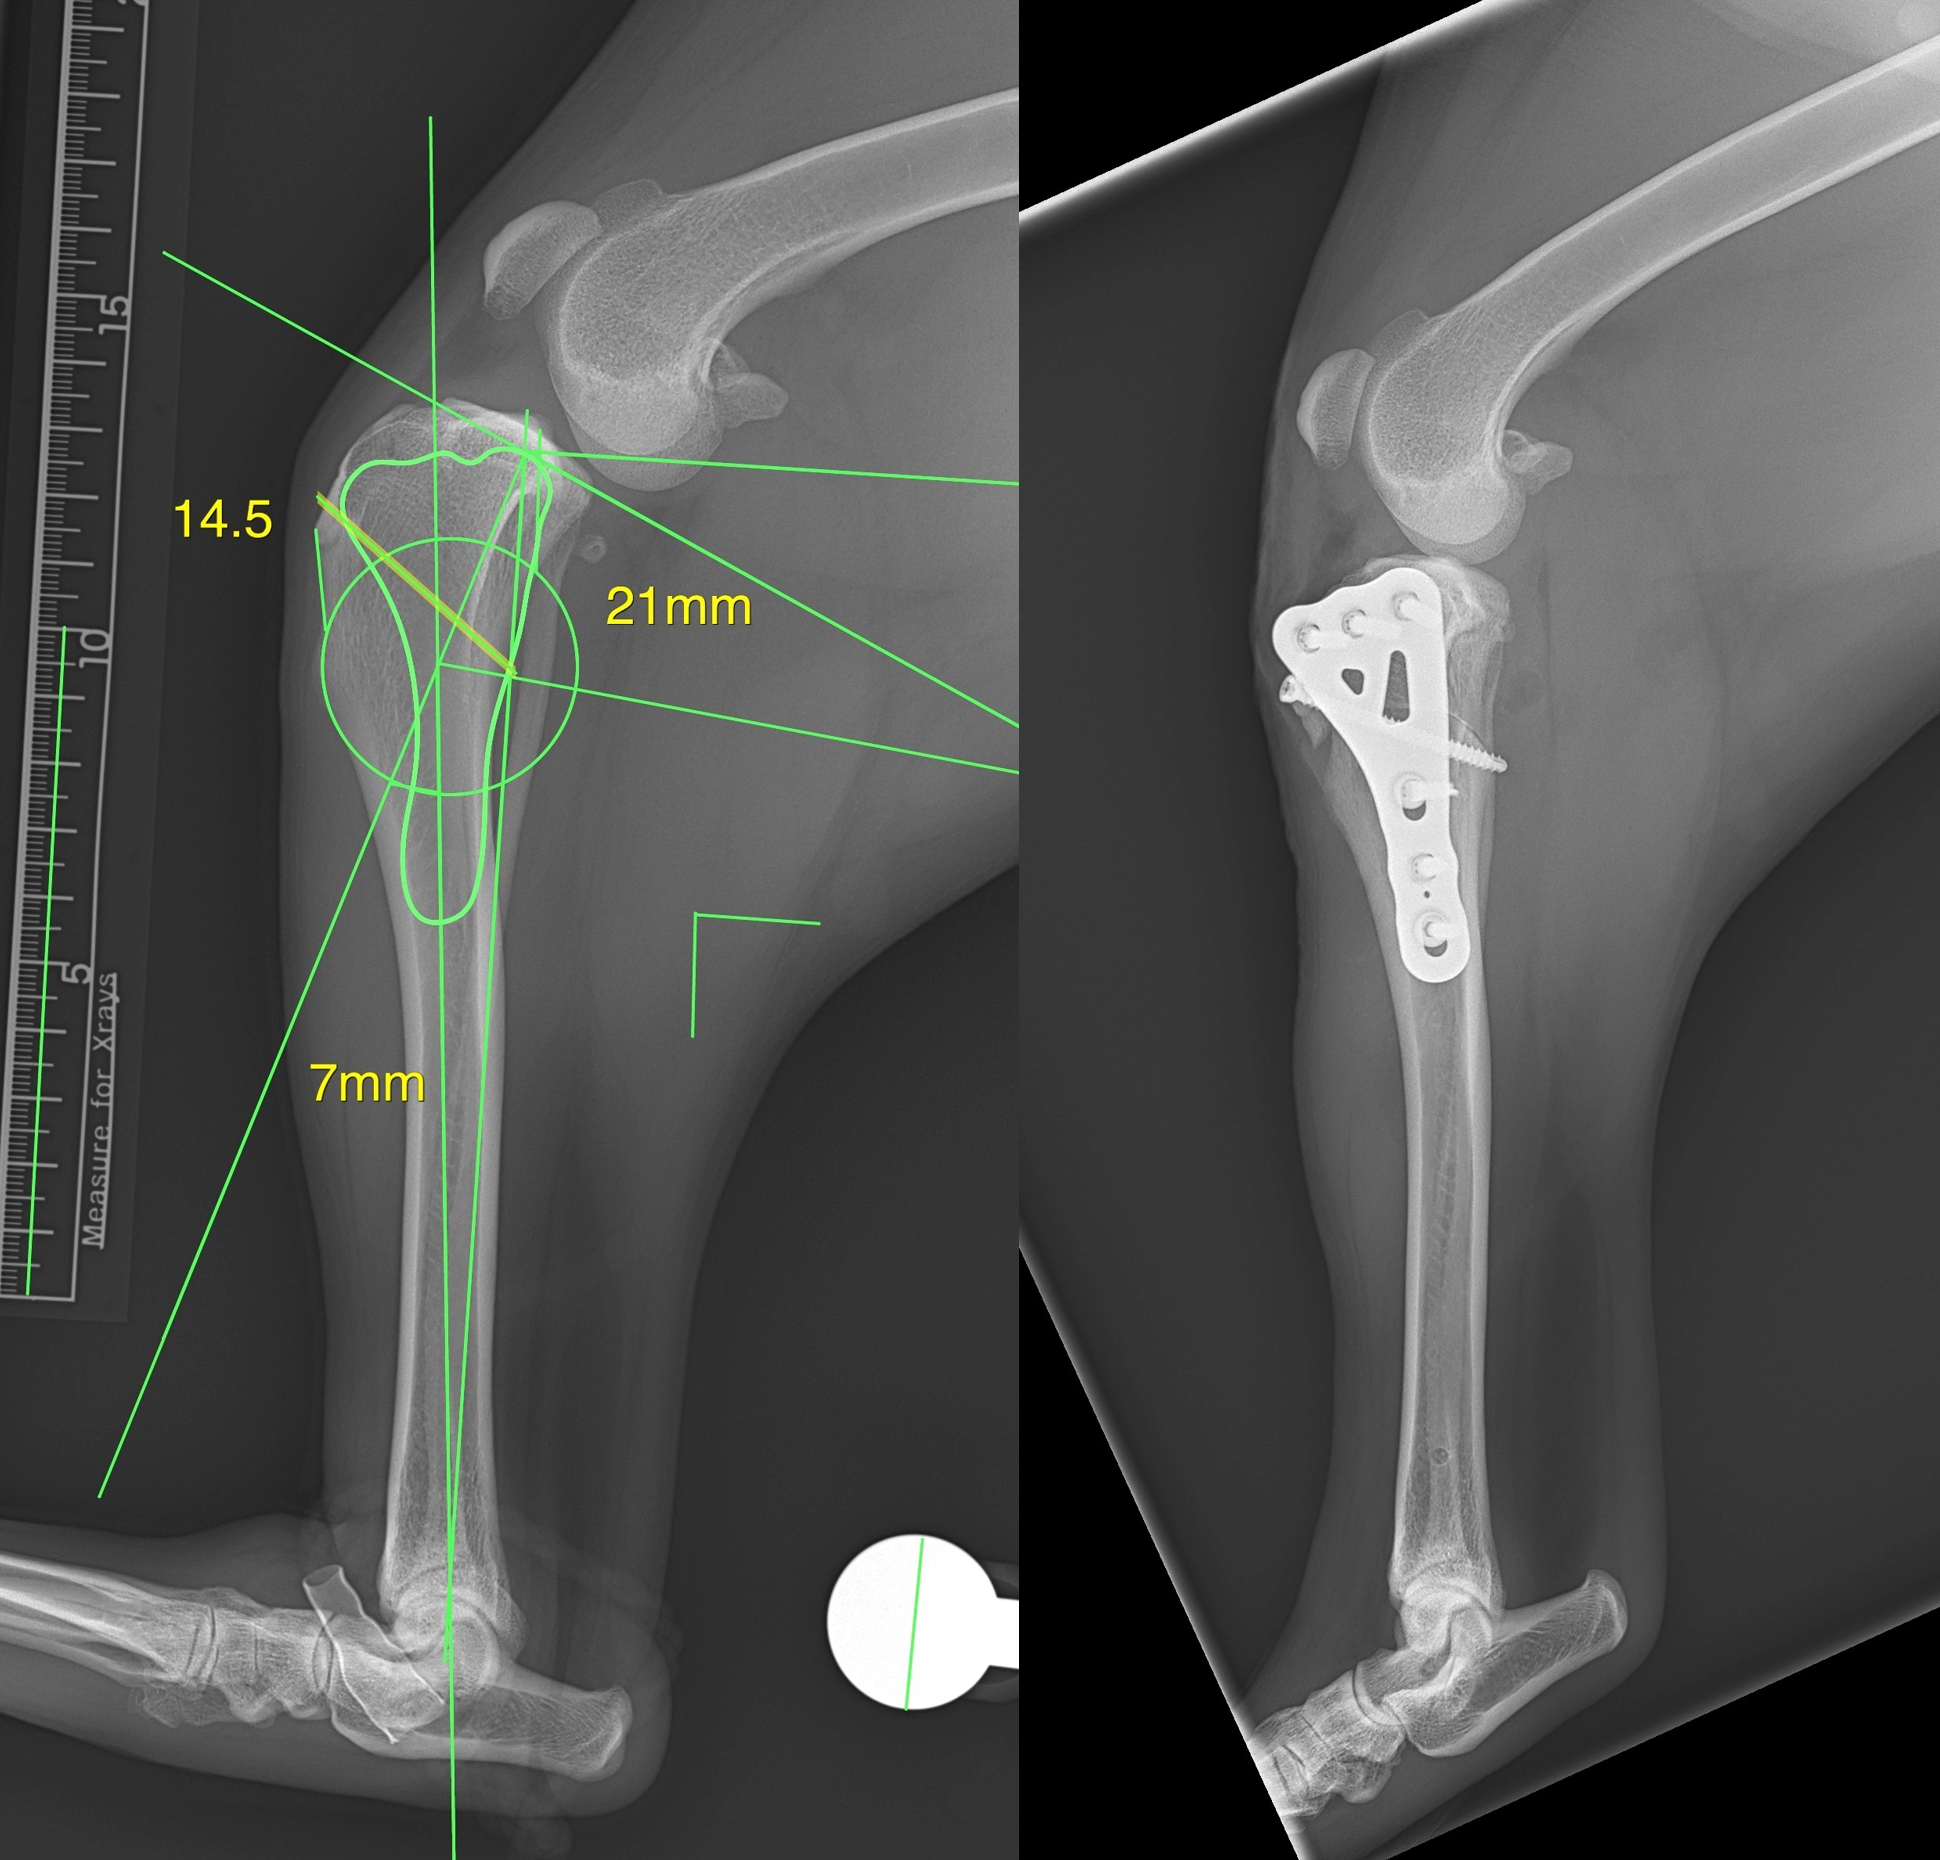

CBLO (CORA-Based Leveling Osteotomy) represents a relatively recent development in treating cranial cruciate ligament (CrCL) injuries in dogs, compared to traditional techniques such as Tibial Tuberosity Advancement (TTA) and Tibial Plateau Leveling Osteotomy (TPLO). It has, however, gained recognition for its efficacy in achieving optimal joint stability and functional outcomes.

The study suggests that CBLO offers biomechanical advantages over TPLO, potentially reducing stress on the caudal cruciate ligament and minimizing cartilage erosion. While long-term studies on larger populations are lacking, results indicate promising outcomes for CBLO, including successful recovery and return to full function within 6 to 12 months post-surgery, even in skeletally immature dogs.

The study evaluated short-term outcomes of CBLO in skeletally immature dogs with CrCL injury, finding favorable results in restoring function. Despite some complications such as proximal tibia recurvatum and valgus deformity, all dogs maintained full limb function following surgery. With proper preoperative planning, CBLO emerges as a viable option for treating CrCL injury in skeletally immature dogs.